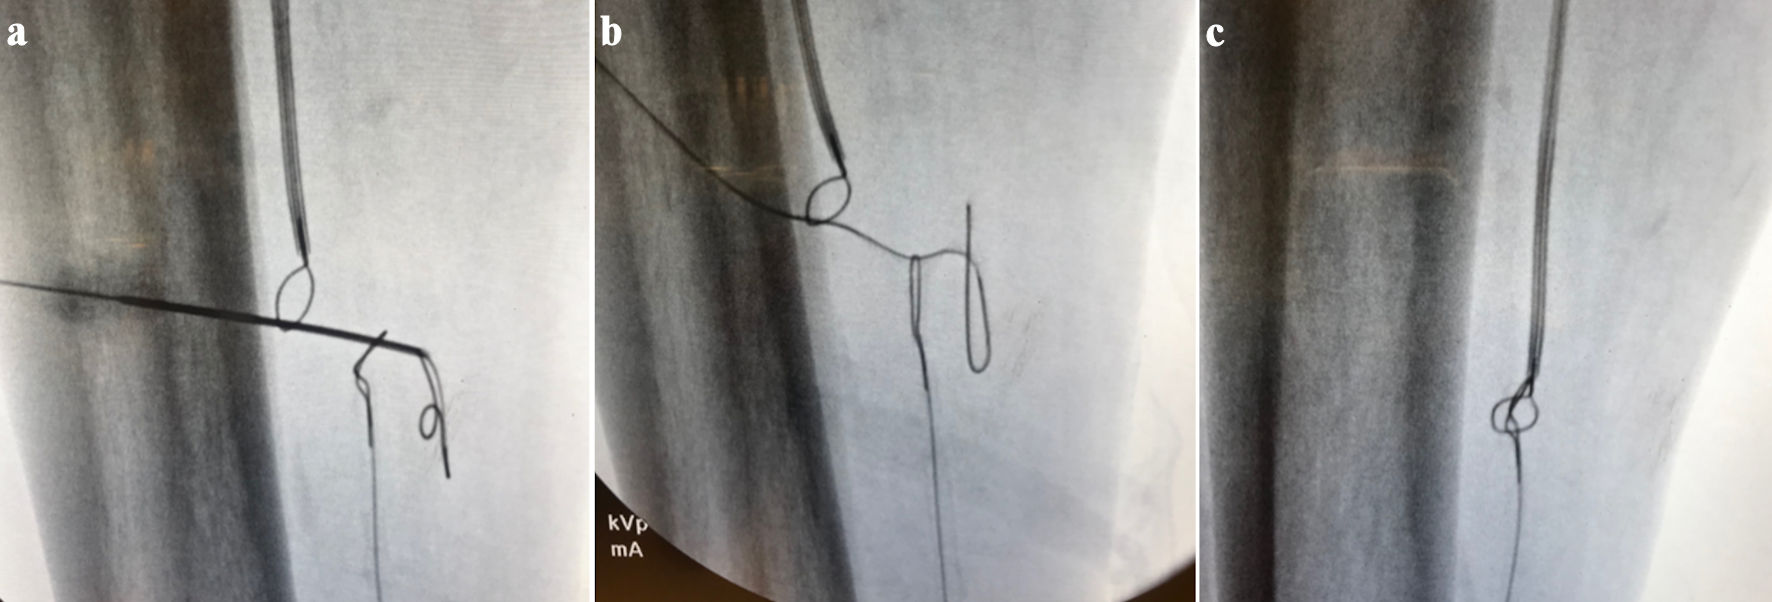

A 7-Fr sheath was inserted antegrade into the CFA and a snare was inserted into the bypass graft. A 6-Fr pedal sheath was inserted retrograde into the distal posterior tibial artery to allow for stable device delivery and retrieval during tract creation. The vessel diameter was adequate to accommodate this size without compromise. Using the double-gunsight technique - a fluoroscopically guided method in which two snares are aligned to target a percutaneous puncture tract - a micropuncture needle was passed through both snares to establish through-and-through access. Distal angiography confirmed a patent plantar arch with in-line flow through the lateral plantar artery and digital branches. A Command 0.018-in wire was flossed through and snared from both ends, enabling angioplasty of the tract with a 4 mm balloon (Fig. 3). A 5 × 100-mm Viabahn stent graft was deployed to bridge the bypass graft to the PTA. A 4-mm balloon was inflated in the bypass portion. The tibial sheath was removed, and through antegrade access, a Command 0.014-in wire was placed into the lateral plantar artery, followed by angioplasty of the PTA with a 2.5-mm balloon and the plantar artery with a 2.0-mm balloon. Post-revision angiography revealed greatly improved blood flow into the arterial plantar arch (Fig. 4). The patient showed signs of healing. At two months post-revision, the patient had avoided amputation and no longer required medication for pain control.

Click for large image

Figure 3. (a) Using double gunsight technique, a micropuncture needle was placed through the skin at the lower leg and through both snares. (b) Command 0.018-in floppy wire inserted in the micropuncture needle, and the needle removed. (c) Floppy wire snared from both ends establishing a tract.